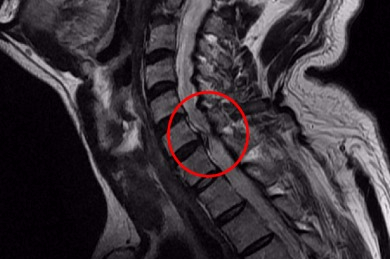

목 뼈와 뼈 사이의 디스크가 제자리에서 이탈되어 신경을 압박하던가 뼈 조직이 비정상적으로 자라 목을 지나는 척추 신경이 눌려 통증을 인지하는 질환이고요.

목 디스크 증상은 어깨, 목 손목등 근육에 통증을 기인하여 인지를 할 수 있다고 합니다. 목디스크 증상 초기에는 하루종일 근육이 뻐근하였거나 찌릿찌릿한 통증이 동반된다고 합니다. 만에 하나라도 경추 가운데 통증을 느끼시는 분들 중에는 지나친 경우 하반신 마비까지 올 수 있기 때문에 조기치료가 필수입니다.

디스크의 수핵이 빠져나가거나 퇴행성 경추 척추증 및 경추관협착증 등으로 척수가 눌리게 되면 거의는 팔의 힘이 빠지는 느낌을 받을 수 있습니다.

드문 드문하게 가슴 쪽에 통증이 일어날수 있고요. 목에서 가슴으로 걸치는 신경이 압박되어 통증이 일어나기 때문인데 하지만 가슴통증은 다른 원인을 통하여도 출현하는 된다면가 많으니 정확히 간파하려면 X-ray를 찍어서 확인하는 것이 좋을겁니다.